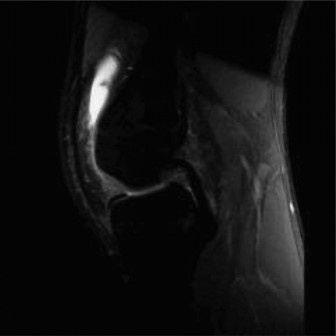

The patient then obtains the following radiograph (Fig. 10–22) which confirms the diagnosis of an OCD lesion of the medial femoral condyle. An MRI is then ordered to examine the lesion further. A T2 image is shown in Figure 10–23.

Figure 10–22

Figure 10–23

The correct answer is (C). The patient has an OCD lesion of the posterolateral aspect of the medial femoral condyle which is the most common location for these lesions. Pediatric patients have a much better prognosis for OCD lesions as open distal femoral physes are the best predictor of a successful outcome with nonoperative management. Lesions which have synovial fluid behind the lesion on MRI are potentially unstable and require much more aggressive surgical management to prevent detachment and separation. As this patient is young, has open distal femoral physes, and has no instability on MRI, a trial of conservative treatment is appropriate. Arthroscopic drilling (either antegrade or retrograde) can be performed for stable lesions which have not responded to a trial of conservative management (Fig. 10–24). Open reduction and internal fixation should be reserved for unstable lesions.